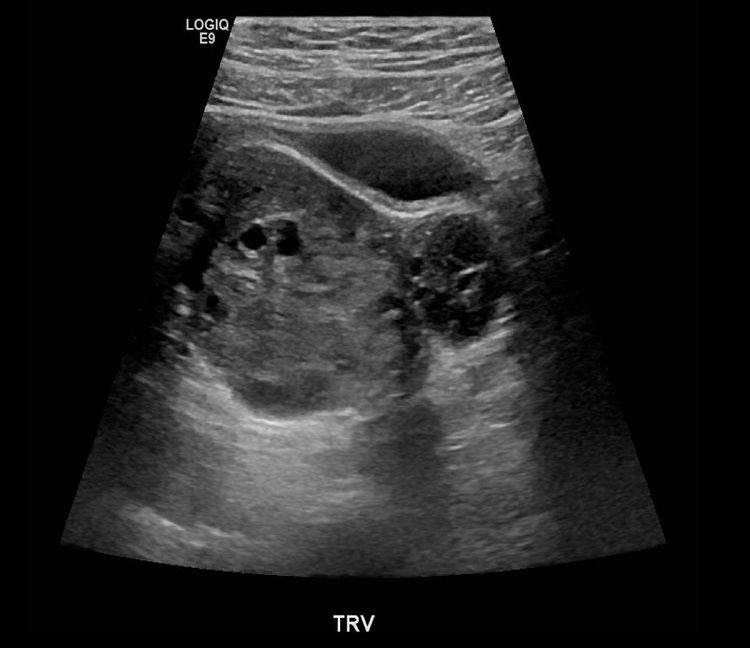

Sonographic findings

- Unilaterally enlarged ovary

- Peripherally displaced follicles due to edema

- Coexistent mass

- Twisted pedicle (not always seen)

- Free fluid

Right ovarian torsion caused by hemorrhagic cyst